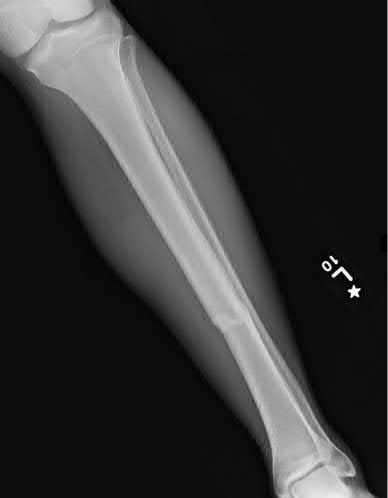

Which of the following fracture patterns is classically associated with varus malunion if treated with closed reduction and casting?

Figure B shows a midshaft tibia fracture with an intact fibula, which places the fracture at increased risk of varus malalignment during healing.

Nonsurgically treated tibial shaft fractures with an intact fibula have an increased risk of varus malunion when treated nonsurgically. The fibula acts as a strut, preventing valgus collapse, but predisposing to varus angulation. Limb-length discrepancies can also occur.

Teitz et al. found that 26 percent of patients over the ago of 20 years old with isolated tibial shaft fractures treated nonsurgically went on to varus malunion. They also found that when the fibula remains intact, a tibiofibular length discrepancy can develop and cause altered strain patterns in the tibia and fibula leading to later ipsilateral joint sequeale.

Bonnevialle et al performed a retrospective study to assess the outcome after reamed nailing of tibial fractures with an intact fibula. Thirty-eight fractures were evaluated at a minimum of one year from surgery. Healing was achieved after the first intention treatment in 30 patients, after dynamization in 6. A non-union in 2 patients was also successfully managed with new nailing and dynamization. The authors concluded that nailing is a reliable technique for the treatment of tibial fractures with an intact fibula.

Sarmiento et al reviewed 1,000 consecutive closed diaphyseal tibial fractures, treated with prefabricated functional below-knee braces, to determine factors predictive of final fracture outcome. They found that final angulatory deformity in any plane was